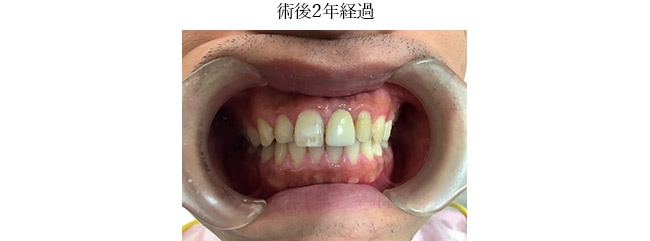

| в‘ҰжІ»зҷӮзөҗжһң | еҜ©зҫҺзҡ„гҒ«гӮӮж©ҹиғҪзҡ„гҒ«гӮӮжӮЈиҖ…гҒ•гӮ“гҒ”жң¬дәәгҒҢжәҖи¶ігҒ§гҒҚгӮӢзөҗжһңгҒЁгҒӘгҒЈгҒҰгҒҠгӮҠе®ҡжңҹжӨңиЁәгӮ’гҒҠйЎҳгҒ„гҒ—гҒҰгҒ„гӮӢгҖӮ |

| в‘ҰжІ»зҷӮзөҗжһң | еҜ©зҫҺзҡ„гҒ«гӮӮж©ҹиғҪзҡ„гҒ«гӮӮжәҖи¶ігҒ—гҒҹзөҗжһңгҒҢеҫ—гӮүгӮҢе®ҡжңҹжӨңиЁәгҒ§пј“пҪһпј”гҒӢжңҲжҜҺгҒ«йҖҡйҷўдёӯгҒ§гҒӮгӮӢгҖӮ |

| в‘ҰжІ»зҷӮзөҗжһң | еҜ©зҫҺзҡ„гҒ«гӮӮж©ҹиғҪзҡ„гҒ«гӮӮжӮЈиҖ…гҒ•гӮ“гҒҢжәҖи¶ігҒ§гҒҚгӮӢзөҗжһңгҒЁгҒӘгӮҠе®ҡжңҹжӨңиЁәгӮ’гҒҠйЎҳгҒ„гҒ—гҒҰгҒ„гӮӢгҖӮгҒҹгҒ еҸҚеҜҫеҒҙгҒ®пј“з•ӘгҒ®з ҙжҠҳгҒҢгҒҠгҒҚгҒӘгҒ„гҒӢеҝғй…ҚгҒ§гҒӮгӮӢгҒЁгӮӮжӮЈиҖ…гҒ•гӮ“гҒ«гӮӮи©ұгҒ—гҒҰгҒ„гӮӢгҖӮ |